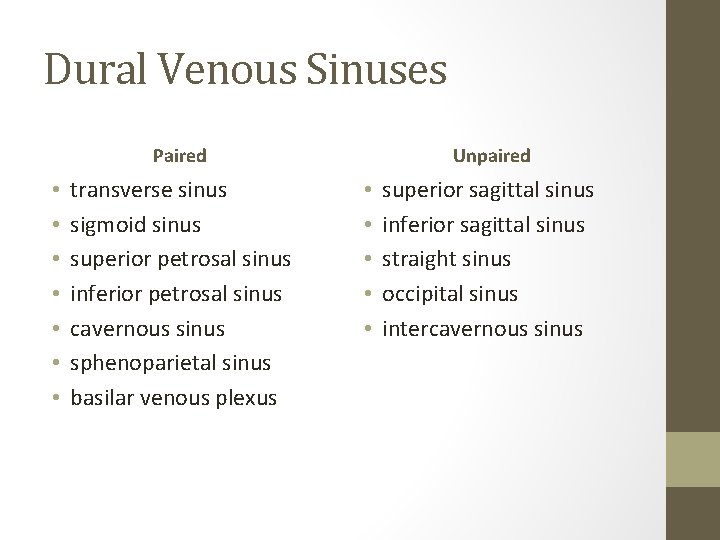

Dural Venous Sinuses Paired • • transverse sinus sigmoid sinus superior petrosal sinus inferior petrosal sinus cavernous sinus sphenoparietal sinus basilar venous plexus Unpaired • • • superior sagittal sinus inferior sagittal sinus straight sinus occipital sinus intercavernous sinus